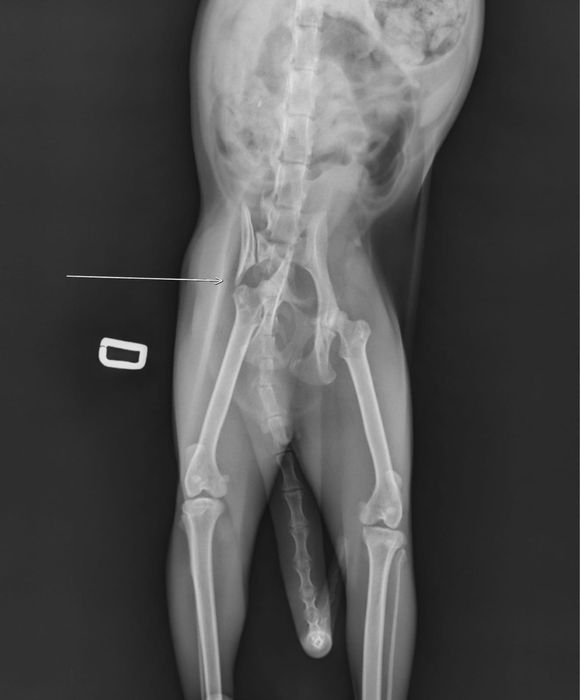

Sasha este o pisică de 6 ani, extrem de iubitoare, care a supraviețuit unui accident grav. A avut bazinul rupt, dar datorită unor oameni inimoși a fost operată, iar acum se recuperează frumos și începe să se miște din nou.